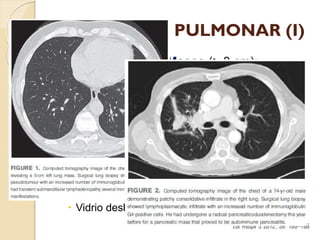

PARÉNQUIMA PULMONAR (I)



Nódulos (≤ 3 cm) / Masas (> 3 cm):

◦ Sólidos / Vidrio deslustrado.

◦ Tamaño:

 < 1 cm - > 5 cm.

◦ Número:

 Únicos / Múltiples.

◦ Malignidad:

 Márgenes espiculados.

 Vidrio deslustrado  Ca. broquioloalveolar.